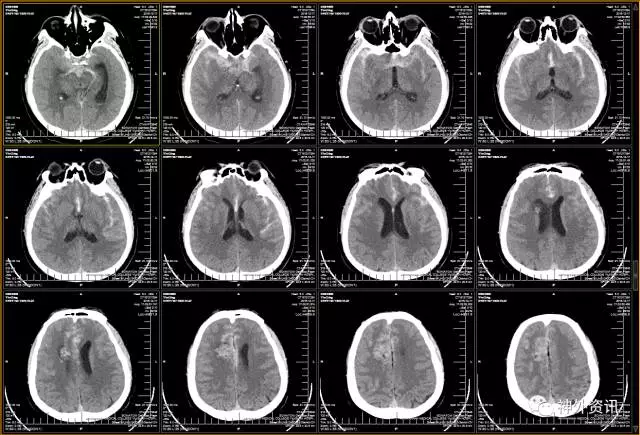

(DSA:烟雾病;左侧大脑后动脉P2段夹层动脉瘤)

(3D重建:动脉瘤形态极不规则,远/近端血管迂曲严重伴狭窄)

(头颅CT:蛛网膜下腔出血,右侧额叶混杂高密度占位伴局部钙化)

(脑动脉CTA:前交通动脉瘤+右侧额叶AVM)

DSA:

(右侧额叶AVM:双侧大脑前动脉+右侧大脑中动脉供血,静脉引流入矢状窦)

(左侧颈内动脉优势供血前交通微小动脉瘤2枚)